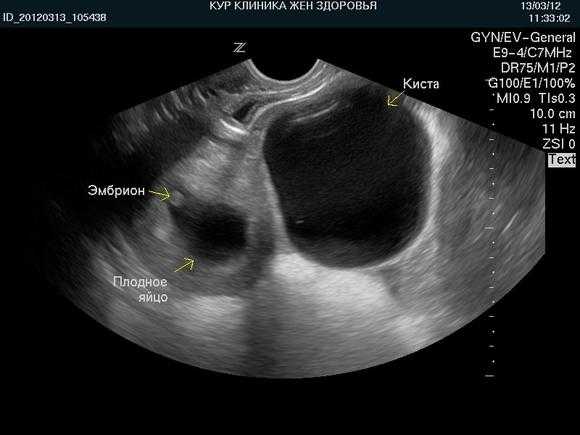

В некоторых случаях киста диагностируется одновременно с беременностью (пример ниже на фото), такое новообразование должно до 20 неделе рассосаться без лечения, так как гормональной фон беременной женщины будет изменяться, и образование лишится необходимой ей подпитки.